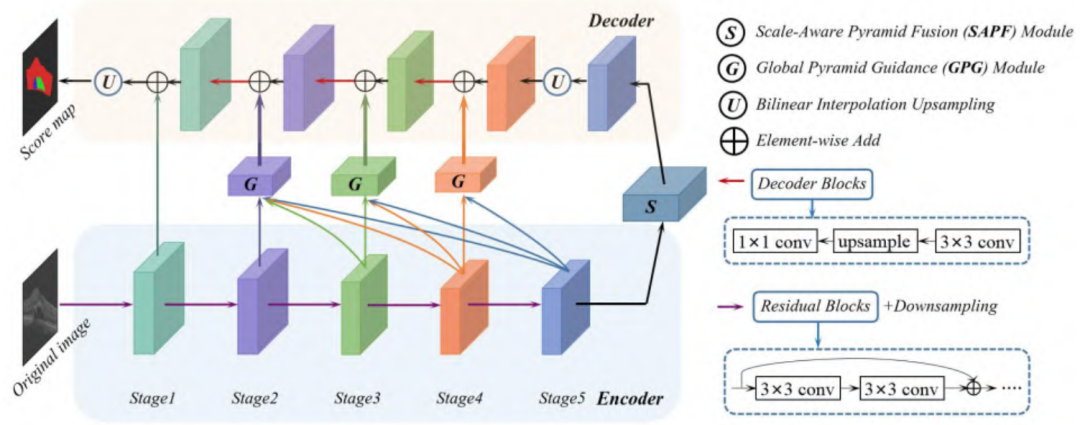

CPFNet

Paper: 《CPFNet: Context Pyramid Fusion Network for Medical Image Segmentation》

Accepted by TMI 2020.

CPFNet,即上下文金字塔融合网络,基于U-Net架构并结合两个金字塔模块来融合全局的多尺度上下文信息。

全局金字塔引导(GPG)模块:通过重构跳跃连接为解码器提供不同层次的全局上下文信息;

尺度感知金字塔融合(SAPF)模块:实现了多尺度上下文信息的动态高层次融合;

实验结果表明,提出的方法在四个不同的挑战性任务,包括皮肤损伤的分割,视网膜线性损伤的分割,胸部器官的多分类分割和视网膜水肿损伤的分割任务上具有很强的竞争力。